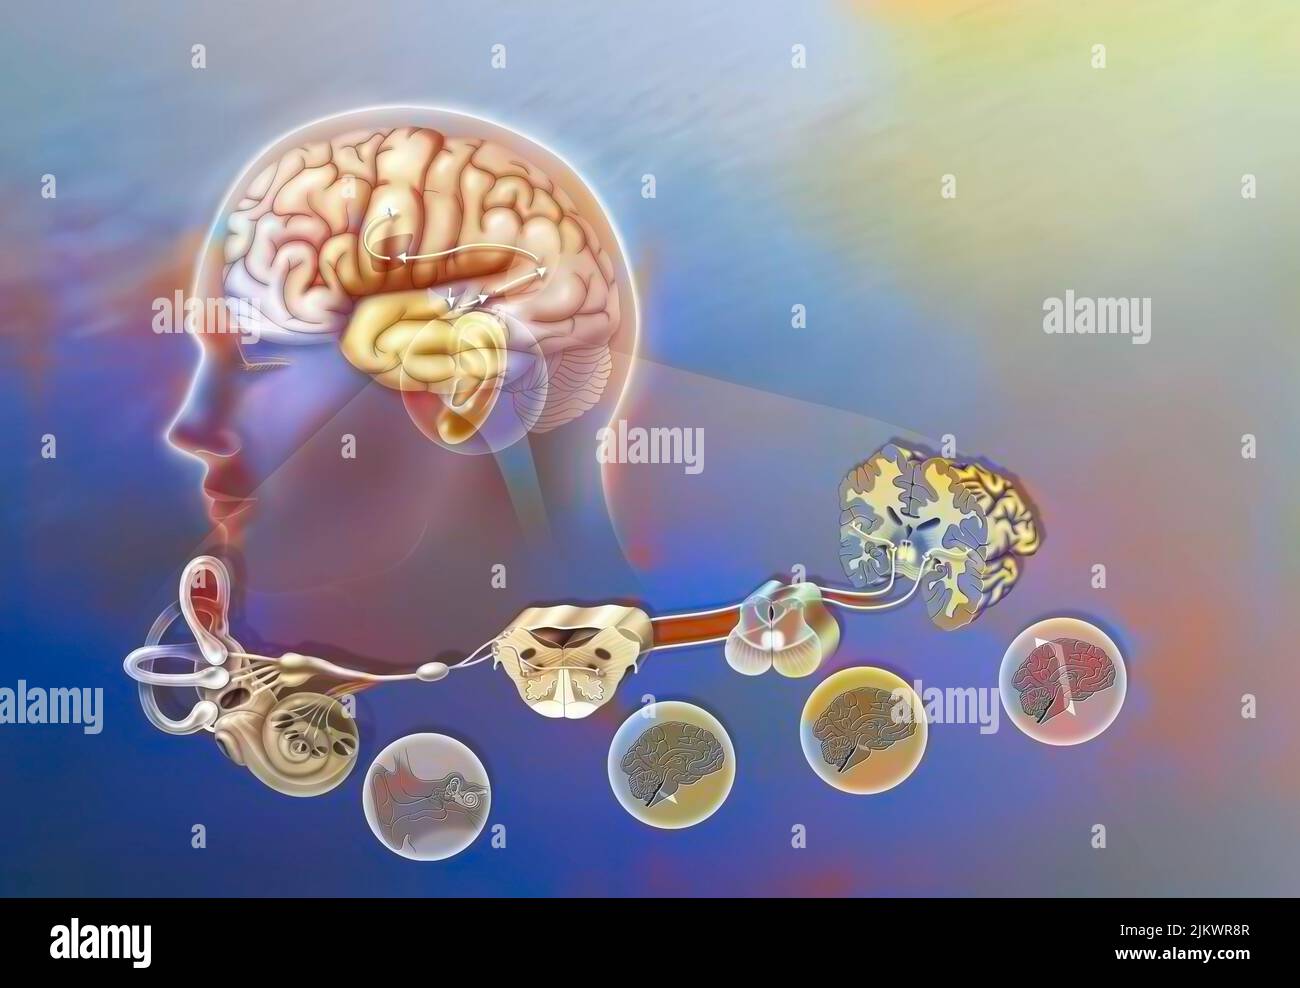

RF2JKWPG7–Troisième étape dans la façon dont le cerveau fonctionne quand vous tombez amoureux: La prise de décision.

RF2JKWPG3–Cerveau dans le chimpanzé avec ses zones (cognitives, auditives, visuelles) et cortex (moteurs, sensoriels).